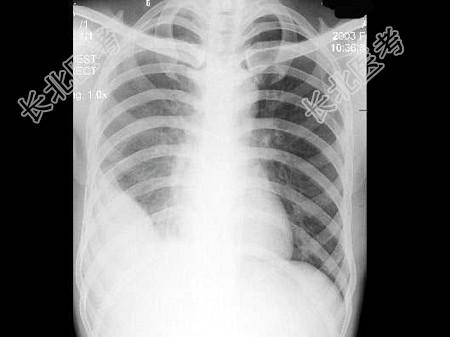

- 单项选择题男,27岁, 近2月来感胸闷,无咳嗽咳痰, 不发热,X线检查如图, 最可能的诊断是 ( )

A、右侧包裹性胸腔积液

B、右侧肺不张

C、右侧游离性胸腔积液

D、右侧膈下脓肿

E、胸膜间皮瘤